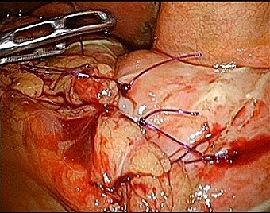

[十二指腸潰瘍穿孔] 手術:腹腔鏡下胃・十二指腸潰瘍穿孔縫合術

手術画像